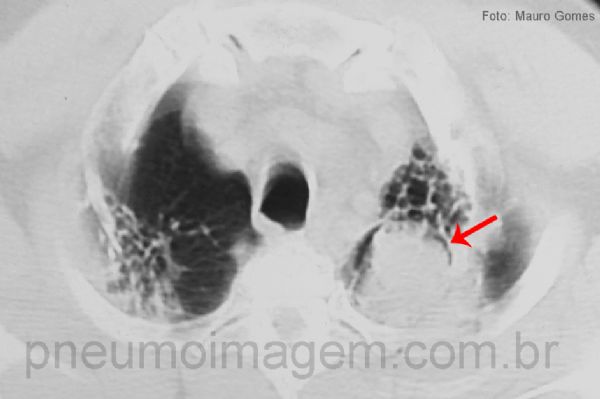

Corte tomográfico mostrando a bola fúngica e o sinal de Monod (seta vermelha).

No lobo superior esquerdo, pode-se observar opacidade que ocupa o ápice do pulmão formando o sinal da crescente, ou meia lua, típico do aspergiloma (seta vermelha).